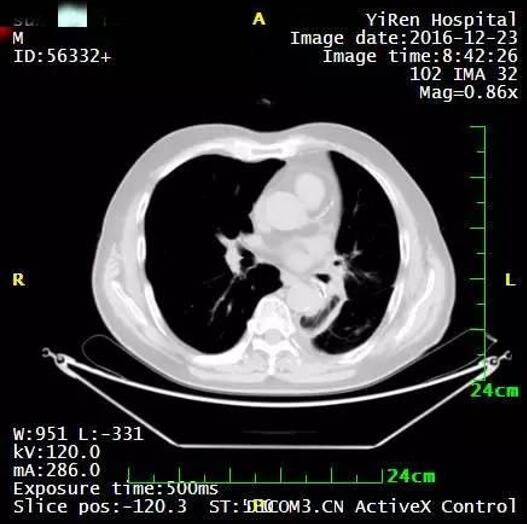

患者男性,64岁。

2016年3月,诊断为小细胞肺癌。

治疗前

治疗后病灶明显缩小

治疗后两个月进一步缩小

治疗后7个月,病灶几乎全部消退